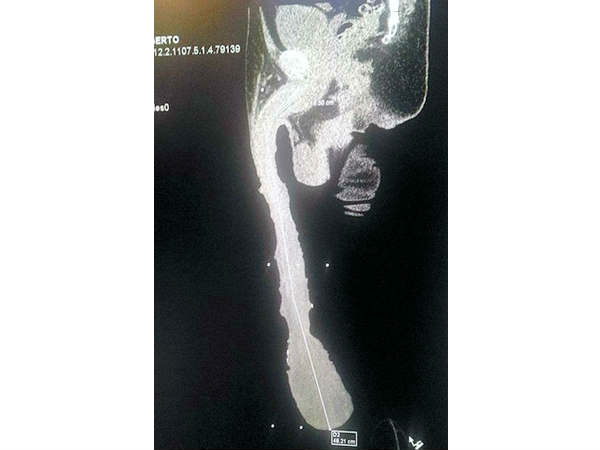

തന്റെ അവയവ വലിപ്പം ഗിന്നസ് ബുക്കില് വരണമെന്ന ആഗ്രഹത്തോടെ ഇത് ഇയാള് എക്സ്റേ എടുത്തു വച്ചിട്ടുമുണ്ട്. ഇത് സത്യമാണെന്നു തെളിയിക്കാന്.

എന്നാല് ഈ വലിപ്പം

എന്നാല് ഈ വലിപ്പം ആഗ്രഹിച്ചു നേടിയതാണെങ്കിലും ഇപ്പോള് ഇയാള്ക്കിതു തലവേദനയാണ്. നീളക്കൂടുതല് കാരണം ഇയാളുടെ മൂത്രം പൂര്ണമായും പുറത്തു പോകാത്ത അവസ്ഥയുണ്ട്. ഇത് അടിക്കടി യൂറിനറി ഇന്ഫെക്ഷന് പോലുള്ള പ്രശ്നങ്ങള്ക്കു കാരണമാകുന്നുമുണ്ട്. ഈ മൂത്രം തുള്ളികളായി വീഴുന്നത് ഒഴിവാക്കാന് ഇയാള്ക്ക് എപ്പോഴും ഈ ഭാഗം മൂടി വയക്കേണ്ട അവസ്ഥയുമാണ്.